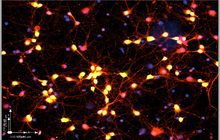

- Immunocytochemistry (ICC) technique

On the other hand, in cutting-edge sciences such as tissue engineering, the use of up-to-date techniques for section preparation and cell tracking and engineered tissue structure has contributed significantly to the development of new studies.